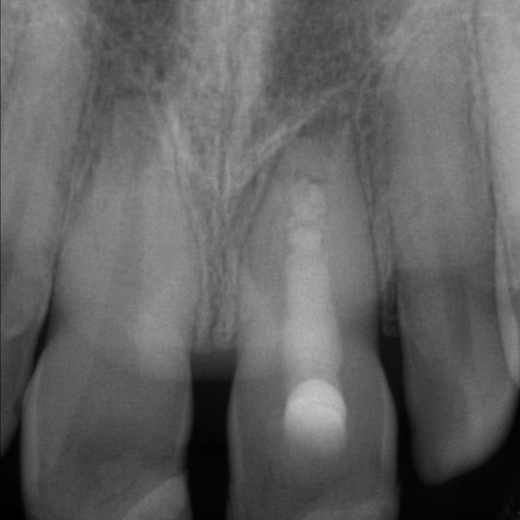

Fallbeispiel: Frontzahntraumata-Trauma im Alter von 9 Jahren mit Recall nach 22 Monaten

Frontzahntraumata sind im Kinder- und Jugendalter nicht selten. Bei noch nicht abgeschlossenem Wurzelwachstum können solche Zähne erfolgreich mit einer Revaskularisation behandelt und erhalten werden.